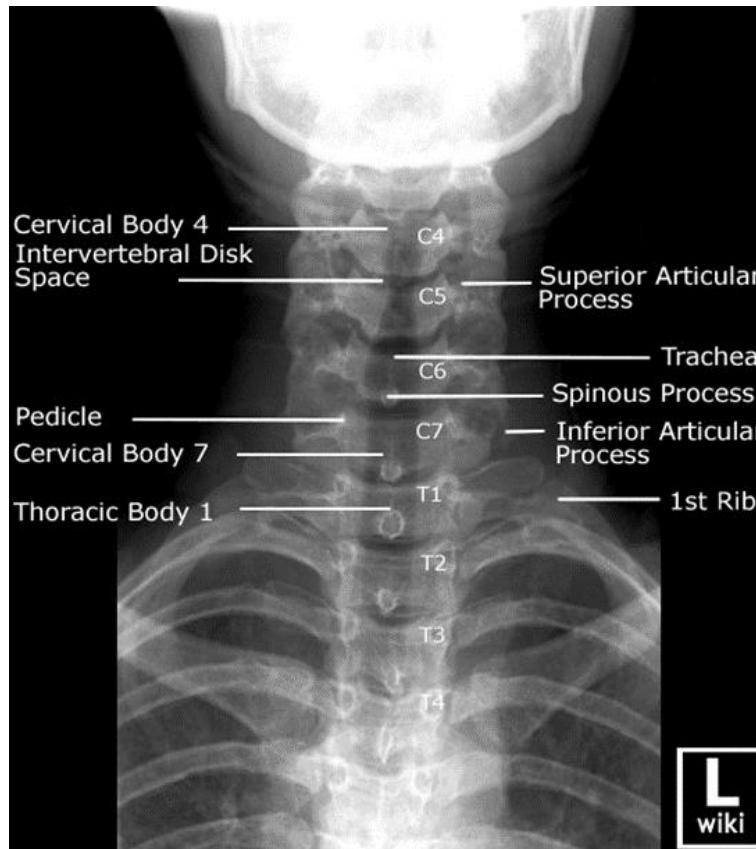

C-Spine X-ray

- Views:

- Lateral View: Must show C1 down to the C7-T1 junction.

- AP View.

- Odontoid (Open Mouth) View: Used to visualize C1 and C2 (especially the dens).

- Pathology:

- Odontoid Fracture (C2): Seen on the open mouth view.

- C2 Fracture (Hangmanโs fracture) can be seen on the lateral view.